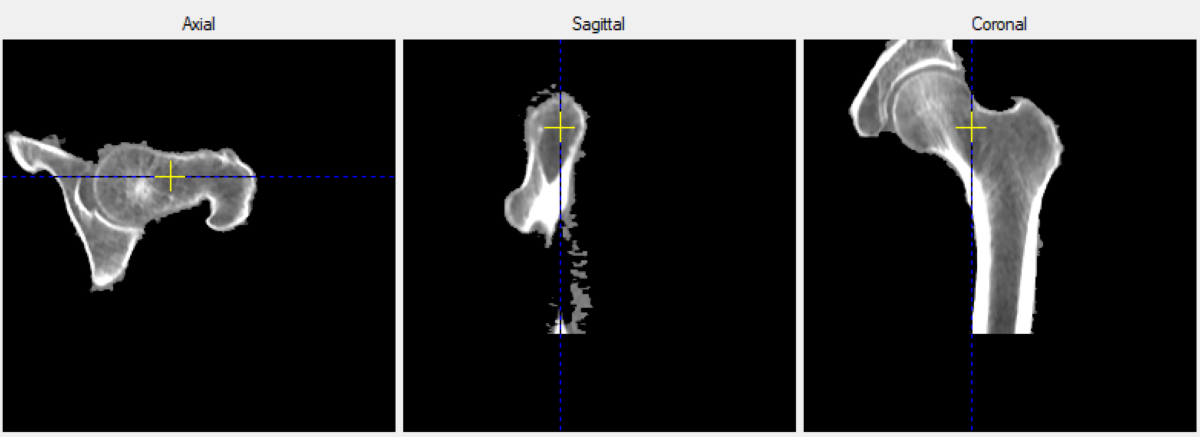

КТ-исследование минеральной плотности бедренной кости. Источник: Наталия Сивакова

Состояние испытуемых ученые оценивали с помощью разработанной ими регистрационной карты. В нее вошли обезличенные данные о возрасте, диагнозе, терапии, перенесенных травмах, наследственности по остеопорозу и образе жизни (курению, употреблению алкоголя, физической активности). Кроме того, у всех участников с помощью компьютерной томографии определили минеральную плотность костной ткани и провели лабораторный анализ показателей минерального обмена.